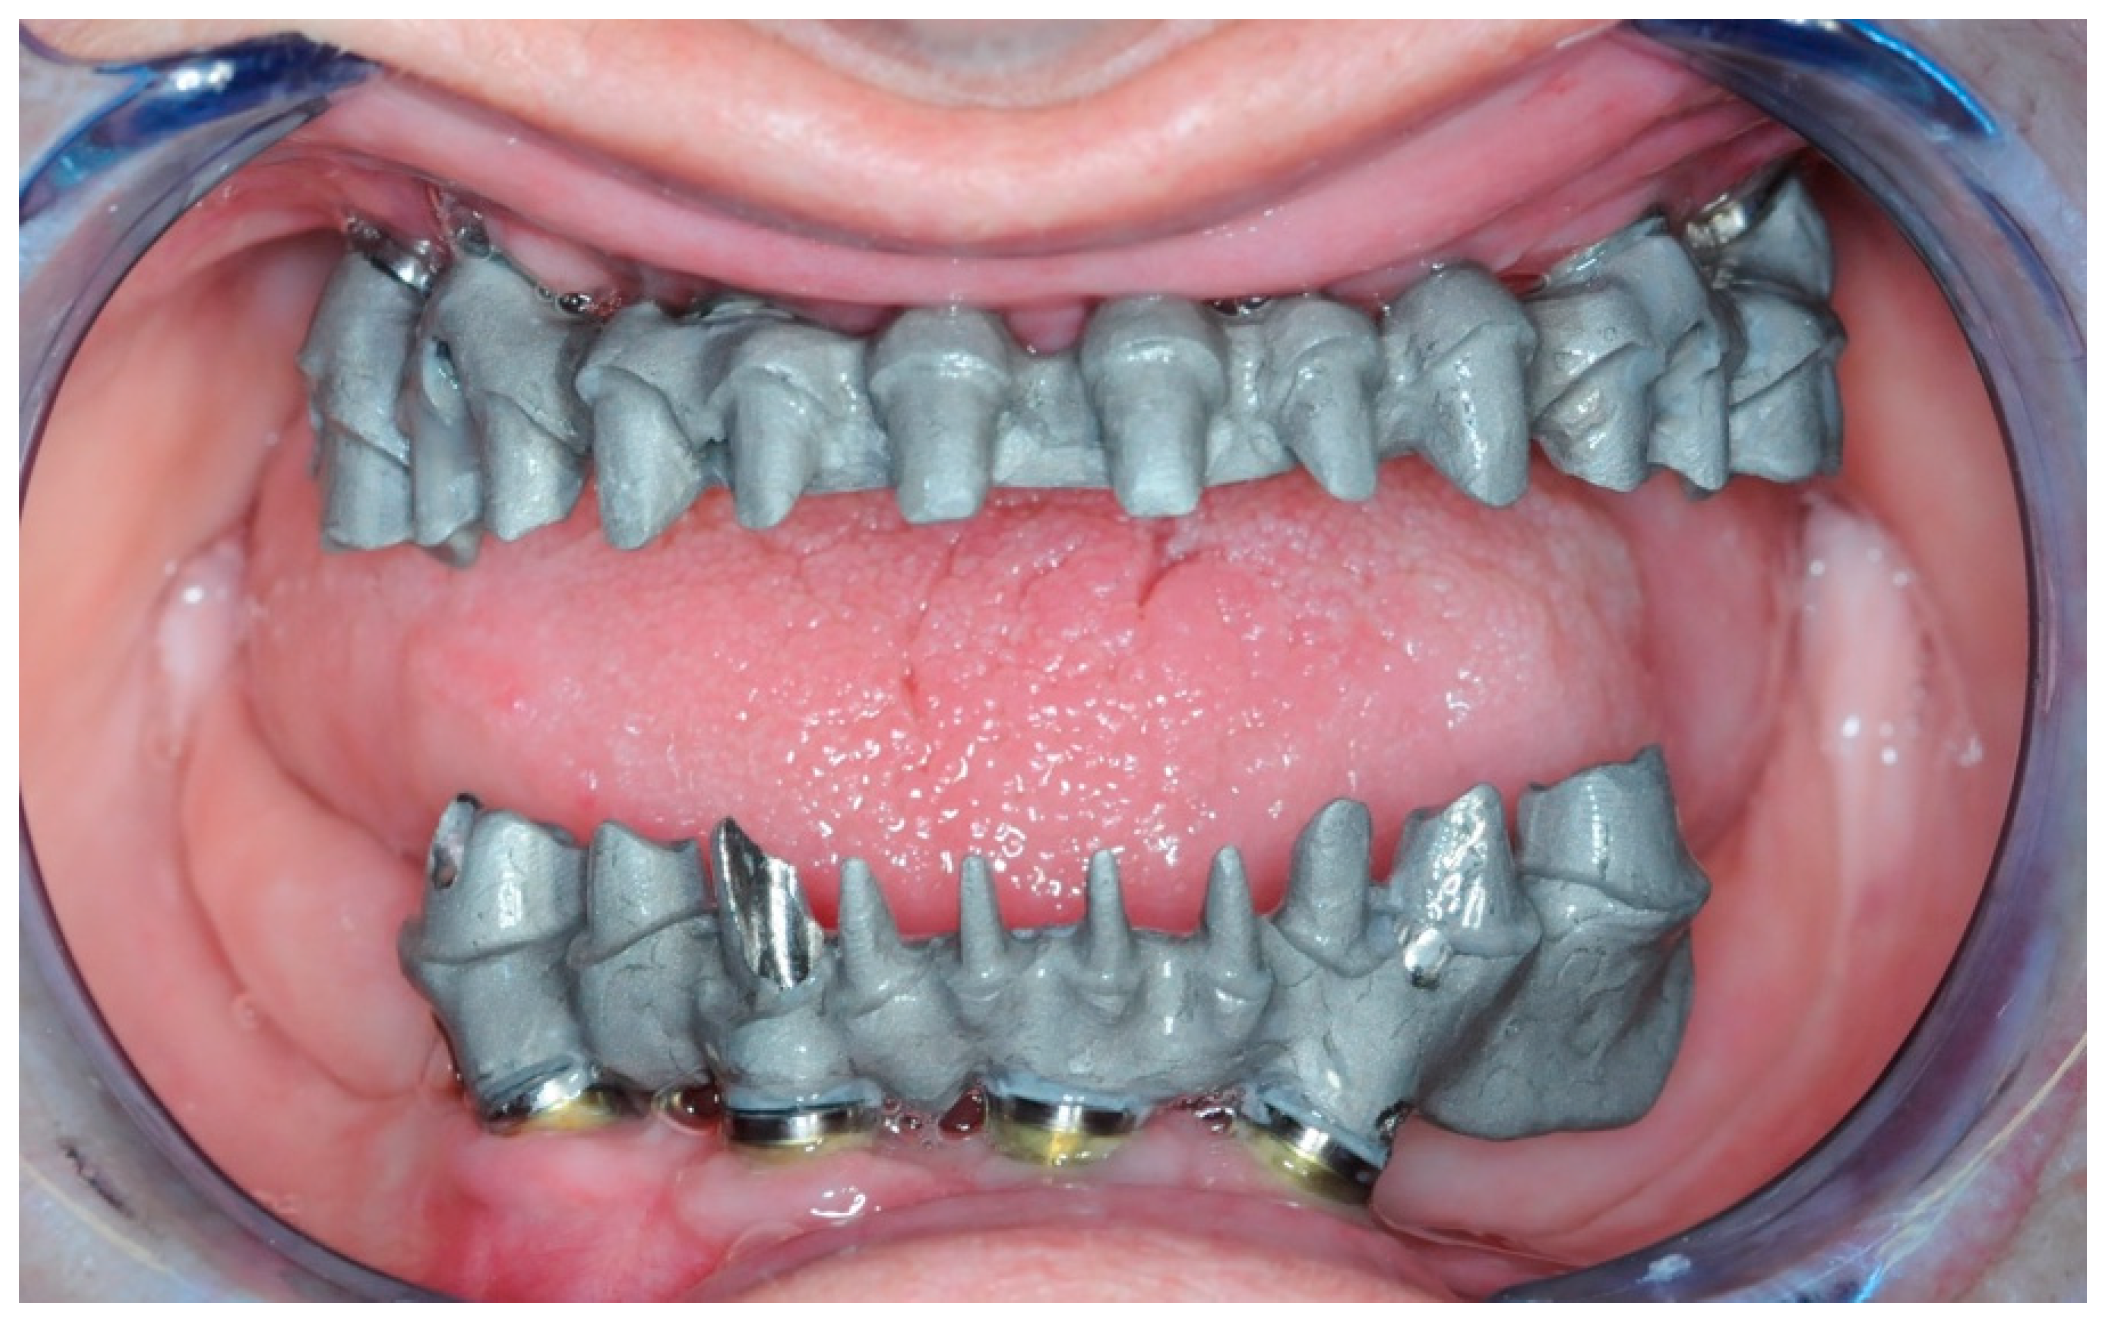

2.4. Temporary Prosthesis

2.5. Final Prosthesis